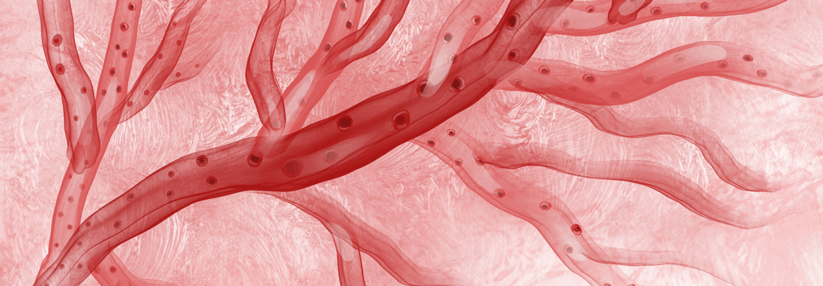

Der Katheter verödet die sympathischen Nervenfasern mittels Ultraschall (rote Kreise). Der Katheter verödet die sympathischen Nervenfasern mittels Ultraschall (rote Kreise). © ReCor Medical. Inc., Medtronic GmbH

In der zweiten internationalen, randomisierten und einfach verblindeten Studie RADIANCE-HTN SOLO setzten die Studienärzte um Dr. Michel Azizi von der Université Paris-Descartes, eine andere RDN-Technik ein und denervierten mittels endovaskulärem Ultraschall.2 Dafür rekrutierten sie Patienten im Alter von 18–75 Jahren mit kombiniertem systolisch-diastolischem Hochdruck, die während der Untersuchung keine Medikamente für diese Indikation einnehmen durften.